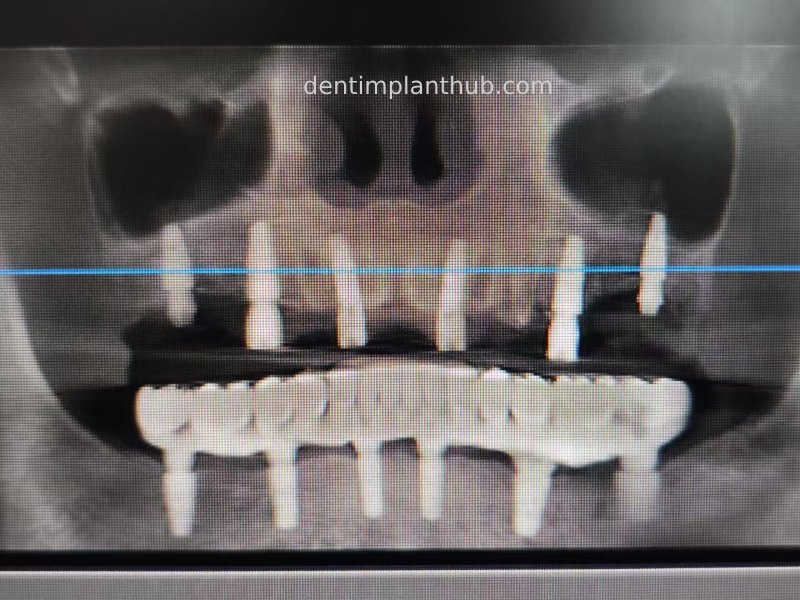

X-ray review panoramic film after surgery on 17/10/23

Post-surgical CBCT review photos

16

14

12

22

24

26